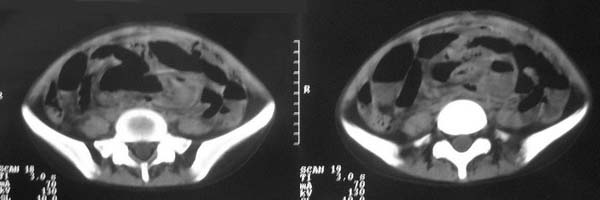

f-18y,腹痛,腹胀,停止排便排气4天,小便正常,四年前阑尾炎手术,病人已手术,明天上传结果。

支持盆腔巨大脓肿。

1,考虑盆腔巨大脓肿;

2,低位肠粘连并梗阻。

直肠左侧低密度模糊影,乙状结肠明显扩张,有宽大液平,下腹部肠袢欠规整,内有多发小液平,结合有阑尾炎手术史考虑:直肠周围脓肿,低位肠梗阻,肠粘连。

盆腔巨大脓肿,据术者讲,脓肿大部分壁是有肠管壁形成的,少部分有自己较厚的壁,子宫、附件都泡在脓液里,腹腔肠管广泛粘连,这个病例奇怪的是急性发病,追问不出慢性病史。